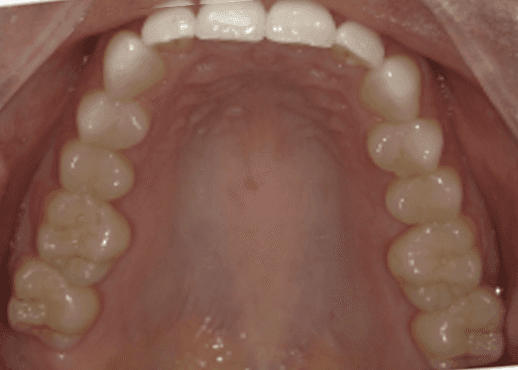

Initial treatment

INTRAORAL